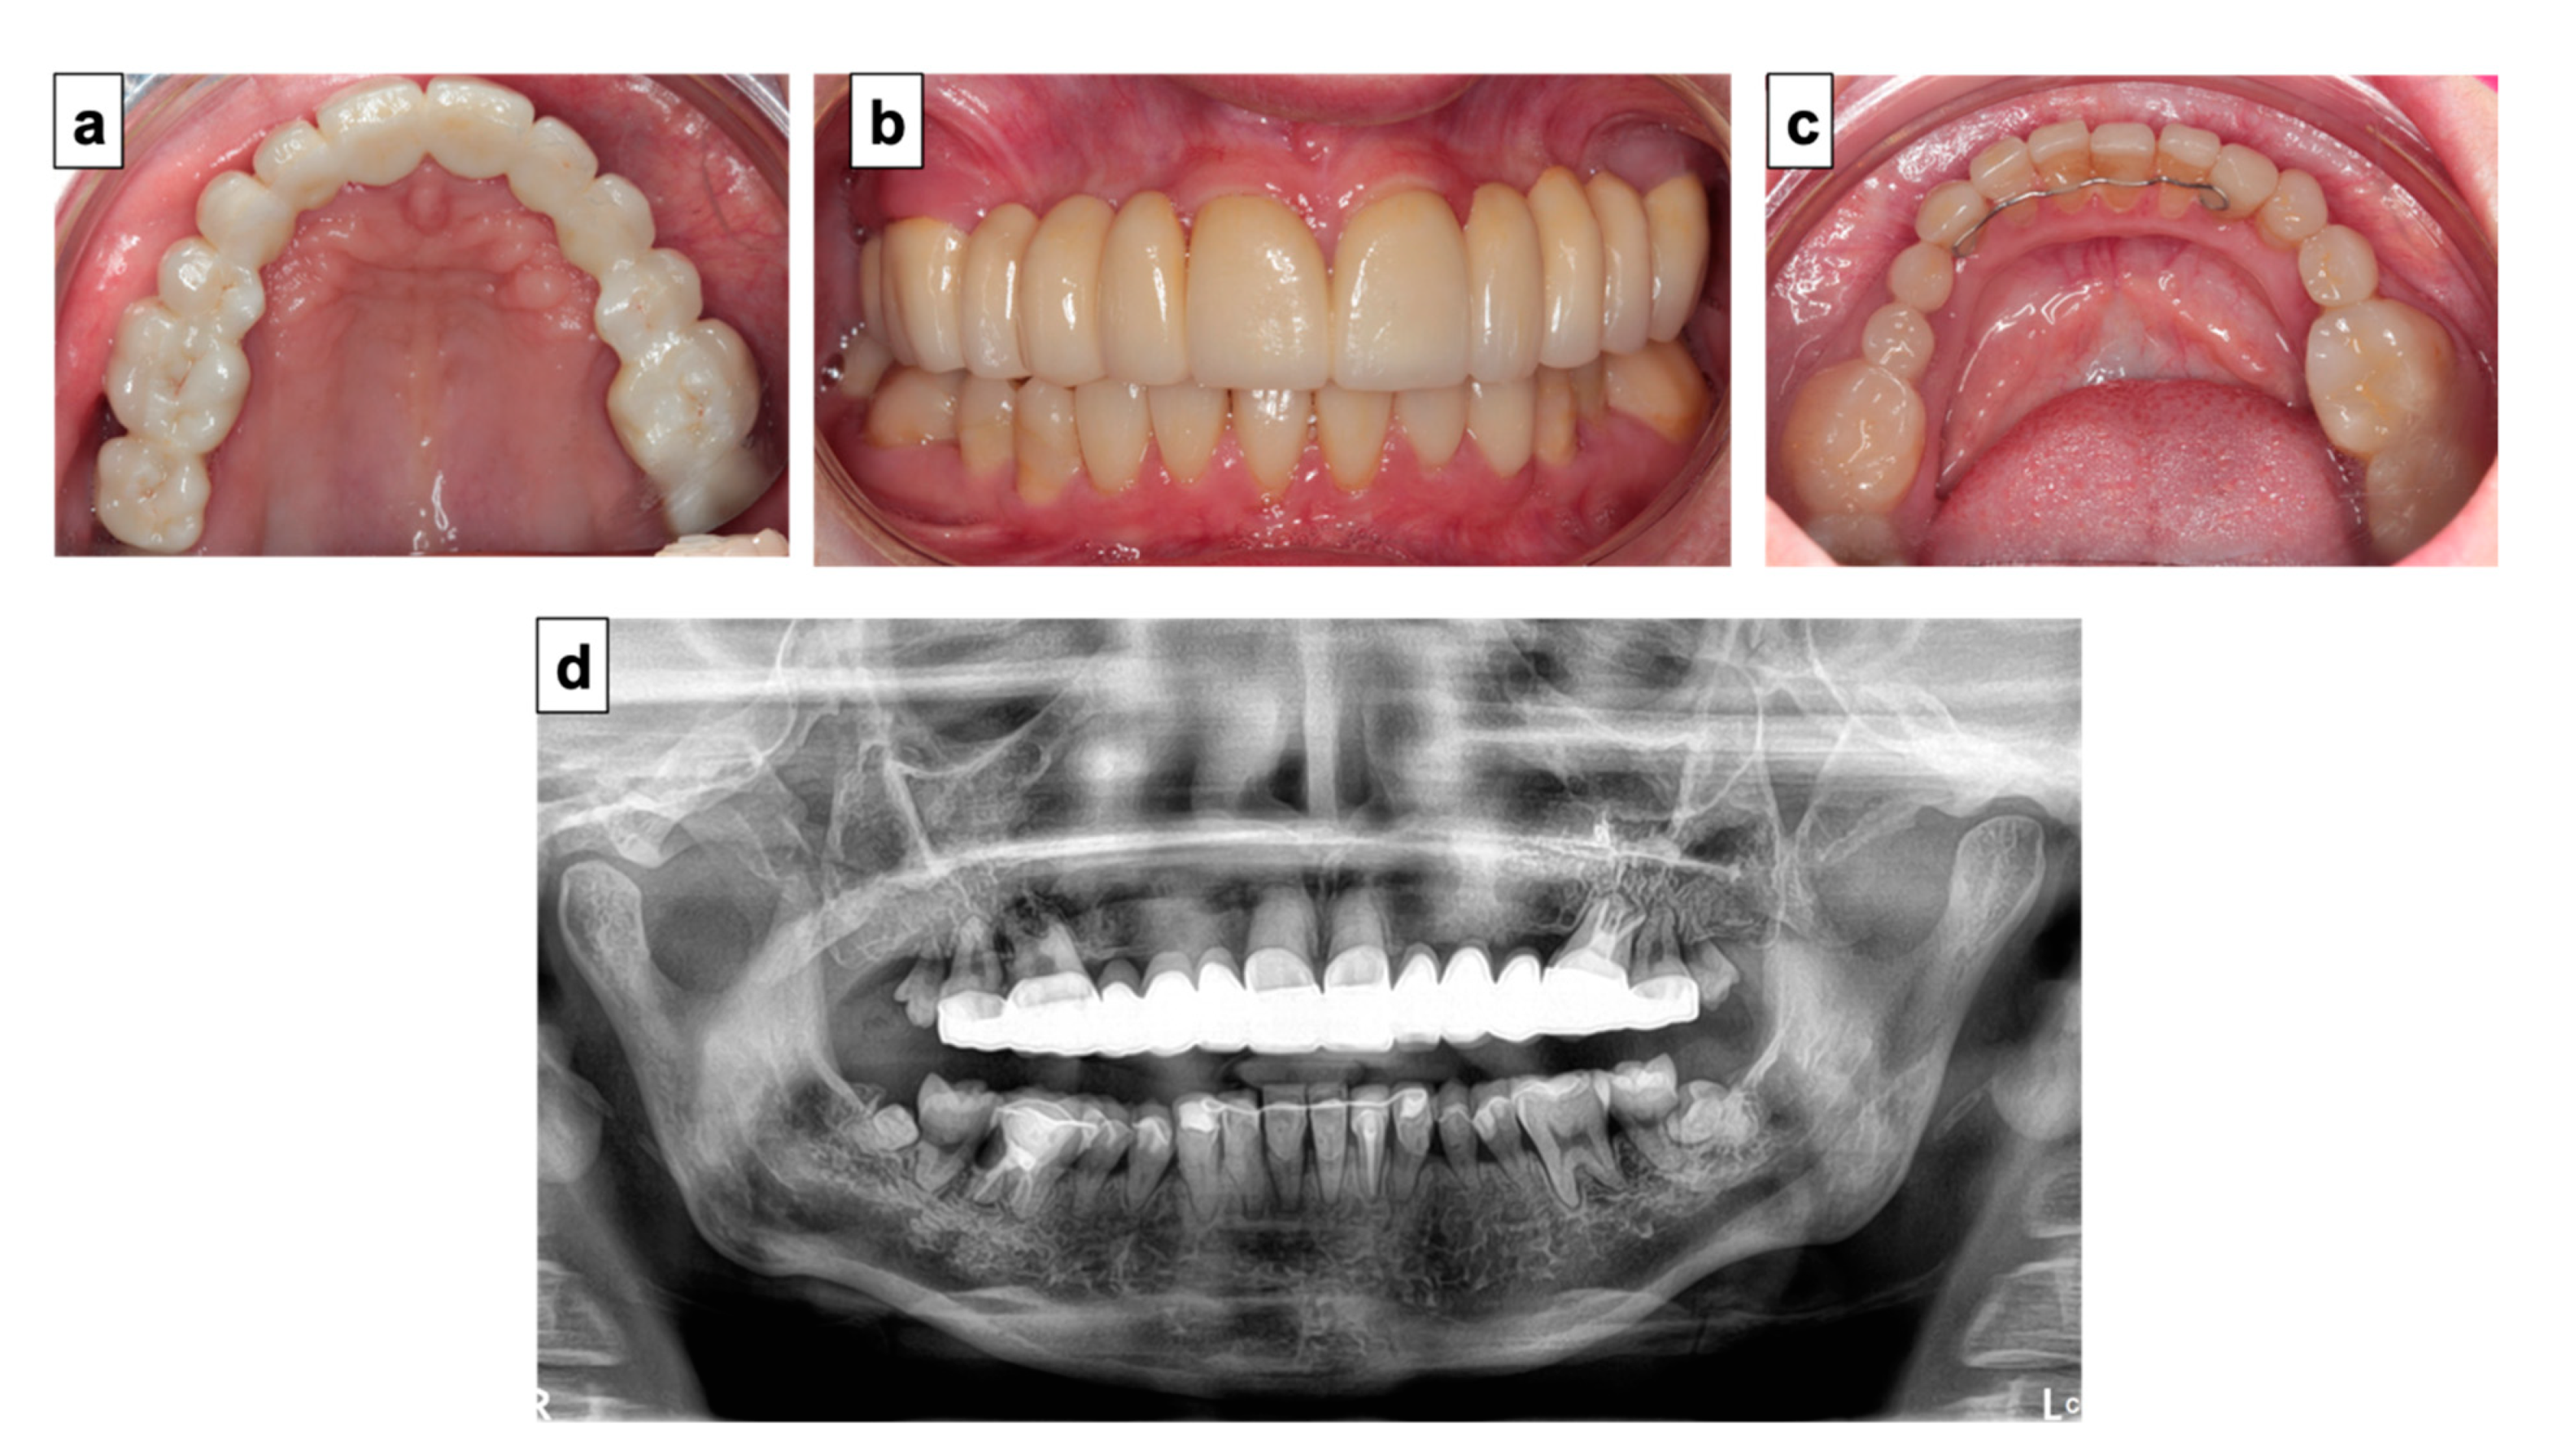

4. Therapeutic Management

5. Discussion

6. Conclusions